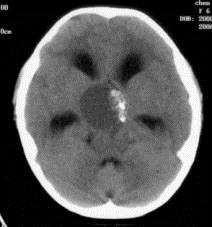

病历摘要:??患者女性,6岁,半年来感觉视力模糊,近10天出现反复头痛,间有恶心呕吐,精神转差,查体:神志清楚,身高90cm,体重25Kg,血压90/55...

问题 病历摘要:??患者女性,6岁,半年来感觉视力模糊,近10天出现反复头痛,间有恶心呕吐,精神转差,查体:神志清楚,身高90cm,体重25Kg,血压90/55mmHg,右眼视力4.6,左眼视力4.8,双侧视乳头水肿,颈软,伸舌居中,四肢肌张力正常,肌力5级,双侧Babinski征(-)。 患者术后第三天,病情加重,检查生化,血钠145mmol/l,尿比重1.010g/l,复查头部CT,发现右侧大脑中动脉供血区域密度减低,右侧脑室受压,蛛网膜下腔、脑室内少量积血,中线有移位,环池显示欠清,这时应采取的治疗措施有?